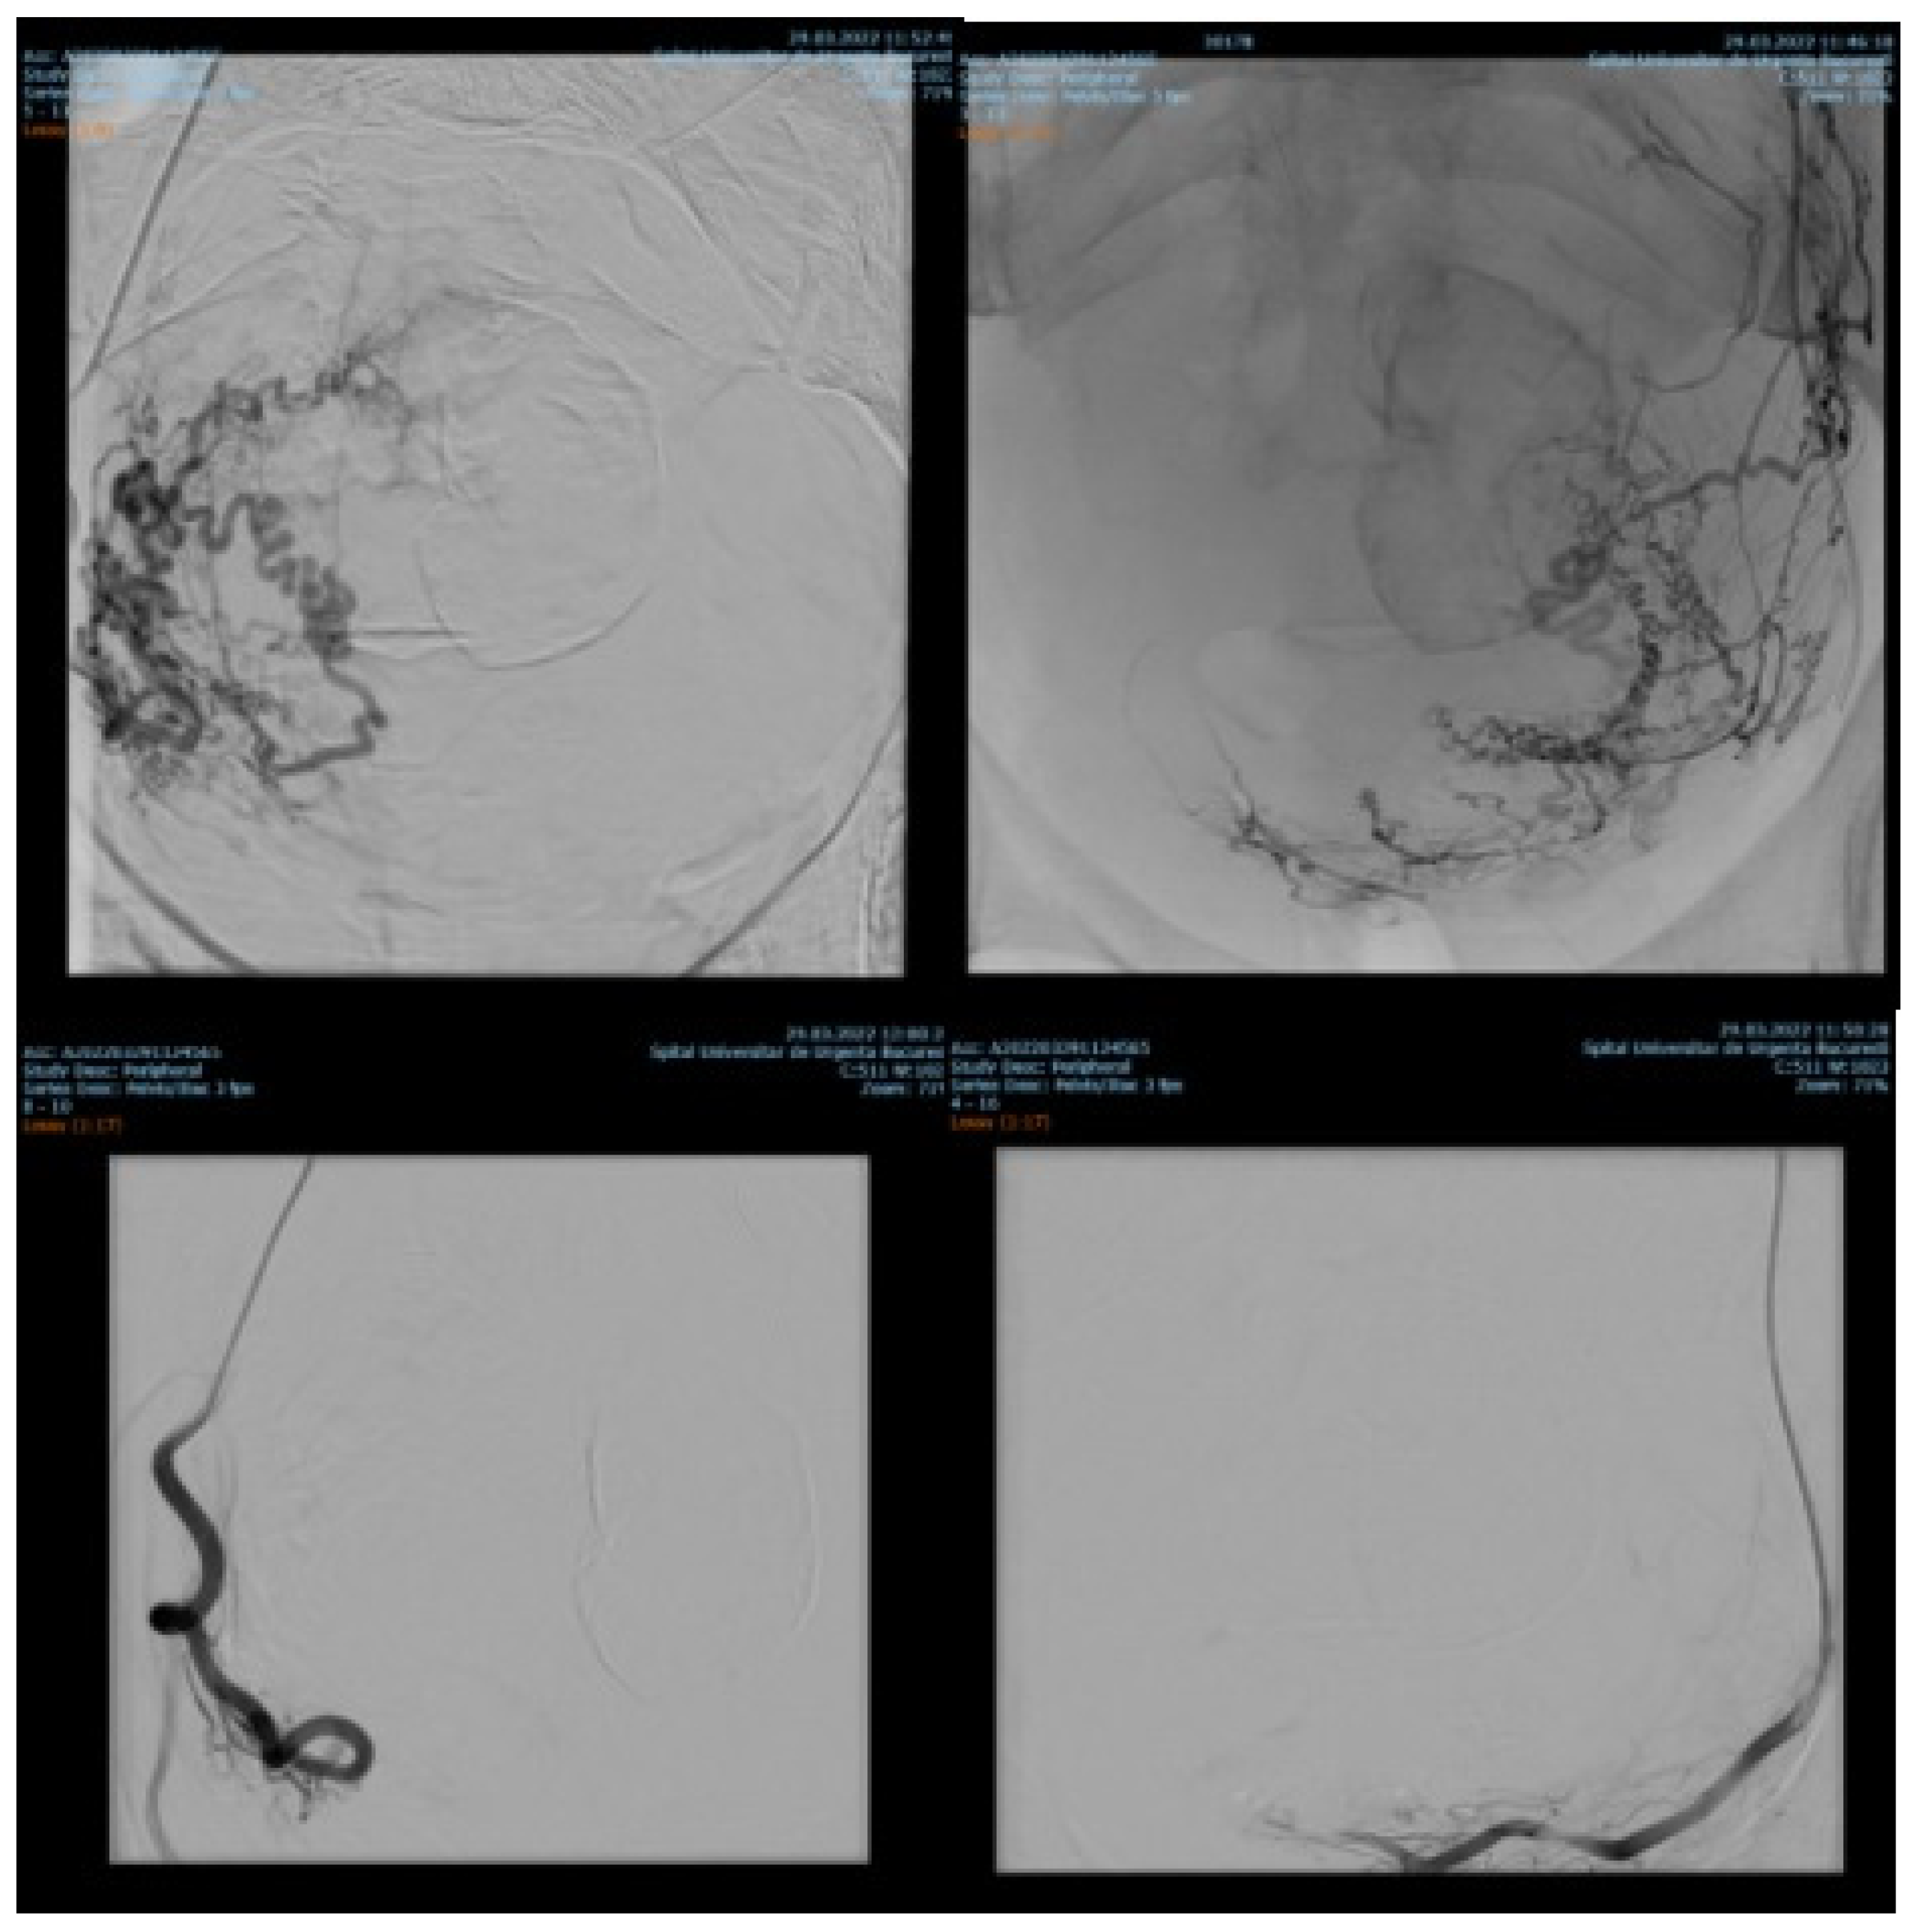

Endovascular procedures were used in 2.29% of cases with ectopic pregnancy (n = 26) (see Figure 4 and Figure 5), 1.23% of patients with arteriovenous malformation (n = 14) (see Figure 6), and 0.52% of patients with major hemorrhage of obstetrical causes (n = 6).

In 97% (n = 1101) of patients, bleeding was stopped after the first attempt of PAE. 3% (n = 34) needed a second embolization. In 12 of 14 cases of AVM, PAE was successful, but in the other two cases, reintervention was needed.

Studies conducted by Jacobowitz et al. and by Ghai et al. support the importance of embolization procedures in bleeding caused by AVM, stating that in some of the cases, re-embolization or even hysterectomy might be needed [2,23,24]. In our study, none of the patients needed hysterectomy, but in two cases we had to reintervene and perform another embolization. Barral et al. concluded that PAE in patients with AVM is effective and does not affect fertility. During the study, they used ethylene vinyl alcohol copolymer [25]. In all our 14 patients with AVM, we used gel-foam, peripherical coils and closure devices.

Figure 6. Selective artery embolization in patient with arterial venous malformation.